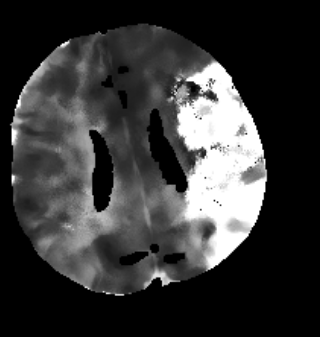

Des Weiteren ist mRay in der Lage eine Verarbeitung von Bildern durchzuführen und so Veränderungen bzw. Anomalien in Geweben zu finden, zu visualisieren und zu quantifizieren. Das Bildverarbeitungsmodul mRay VEOcore kann verwendet werden, um Bilder des Gehirns von Bildgebungsmodalitäten wie CT, Perfusions-CT oder MRT mit diffusionsgewichteter Auswertung (DWI) zu prozessieren. Als Ergebnis werden Kontrastveränderungen über die Zeit als farbige Perfusionskarten angezeigt, dies beinhaltet auch flussbasierte Parameter und Gewebeblutvolumen Berechnungen.

Die Perfusionsanalyse von Aufnahmen des Gehirns ermöglicht die Darstellung und Quantifizierung von minderdurchblutetem Gewebe (Penumbra), nicht-durchblutetem Gewebe (Kerngewebe) und dem Mismatch-Ratio zwischen den beiden Werten. Die berechneten Werte können der Unterstützung bei einer Entscheidungsfindung dienen, die auf der Beurteilung des Ausmaßes der Schädigung von Geweben basiert.